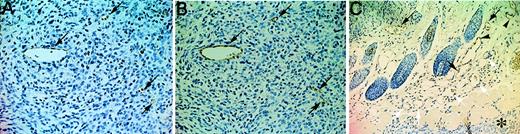

Such a dramatic suppression of tumor growth by AFL4 treatment implicates the role of VEGFR-3 in angiogenesis rather than in the formation of lymphatic vessels, though VEGFR-3 is not expressed in the blood vessels of normal tissues. Thus, we hypothesized that VEGFR-3 expression might be induced by tumor transplantation in the surrounding tissue. To test this possibility, we investigated VEGFR-3 expression in the tumor-bearing tissues. Sections of tumor and surrounding tissues were immunostained with AFL4 or anti-PECAM-1 mAb. VEGFR-3 expression was detected in intratumoral vessels (indicated by arrows) (Figure5A). Unlike normal tissues (Figure 3E), VEGFR-3+ vessels in this section contained blood cells, indicating that VEGFR-3 expression was induced in the tumor blood vessels. A similar staining pattern was seen for PECAM-1 staining of serial sections, demonstrating EC-specific expression of VEGFR-3 (Figure 5B). It should be noted, however, that not all EC in the tumor vessels expressed VEGFR-3. Intratumoral VEGFR-3+ vessel density, including lymphatics, was 30 ± 1.2 per high-power field, whereas that of normal skin tissue was 7.4 ± 0.3 per high-power field. Because the intratumoral PECAM-1+ vessel density was 92 ± 2.8, approximately 30% of intratumoral vessels become activated to express VEGFR-3+, and because PECAM-1+ vessel density in the normal skin was 38 ± 1.3, the intratumor region was indeed rich in blood vessels. VEGFR-3 staining was also induced in vessels surrounding the tumor (Figure 5C).

Induction of VEGFR-3 expression during tumor-induced angiogenesis.

Immunostaining for VEGFR-3 (A) and PECAM-1 (B) in adjacent sections of C6 subcutaneous tumors (day 7) in nude mice (×200). Intratumoral VEGFR-3+ (A, arrows) containing blood cells are also positive for PECAM-1 expression (B, arrows). Note that hemorrhages are not conspicuous at this stage. (C) Immunostaining for VEGFR-3 in a section of C6 tumors with surrounding tissues (×100). Note the presence of VEGFR-3+ (black arrows) and VEGFR-3−(white arrows) vessels, both containing hematopoietic cells. Arrowheads indicate VEGFR-3+ vessels that do not contain hematopoietic cells. Asterisk indicates the edge of a tumor.